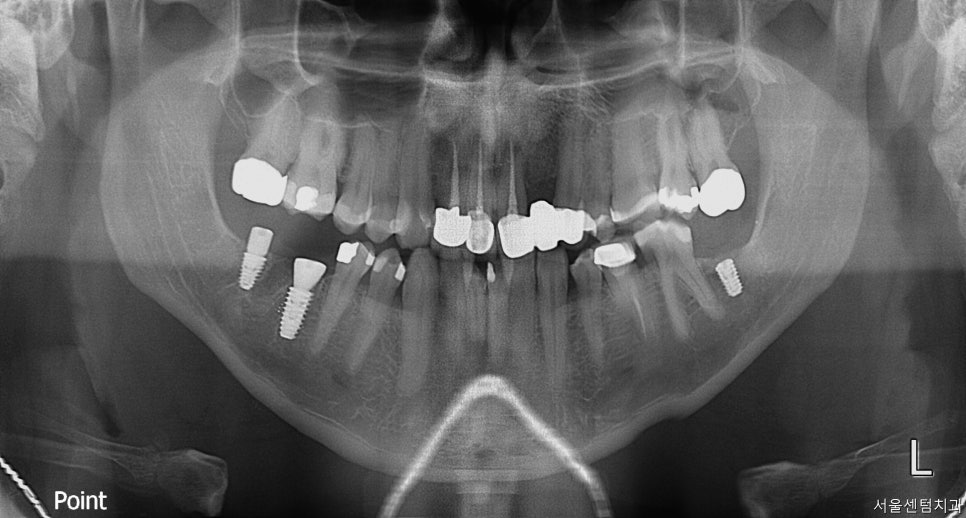

바로 파노라마 촬영을 진행하였습니다.

문제가 있던 치아는 #46번 치아는 깨져서 오셨고

#47번은 안좋아서 이미

발치 하신지 좀 되셨다고 하셨습니다.

반대편 #37번도 안좋아서 발치 하셨는데

계속 치아가 없는 상태로 있다보면

그 위에 맞닿아 있는 #17번 #27번 치아도

내려올 수 있는데 이미 조금 정출되어 보여

빨리 임플란트를 하시는 걸로 얘기드리고 당일날

바로 수술 진행하였습니다.